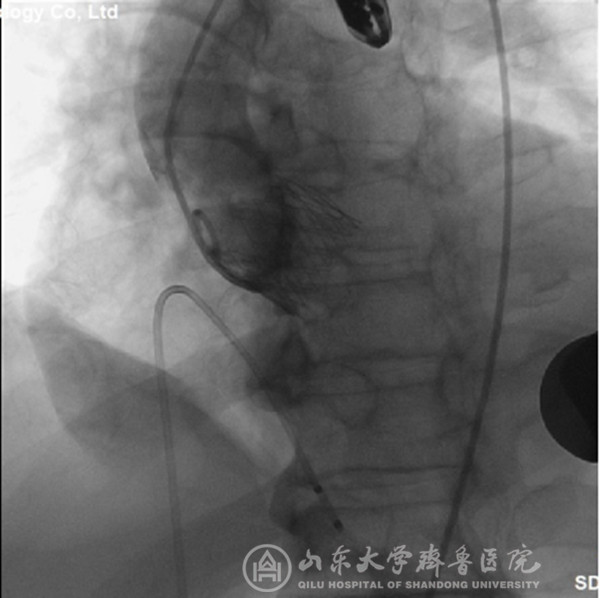

经过充分细致地准备,TAVI团队在复合手术室实施手术。根据患者的病情特点,术中做好各种应急预案,备好体外循环,维持血流动力学平稳。根据术前CT分析和术中主动脉根部造影情况(图1),选择最佳投照体位。选用29mm的介入主动脉瓣膜,经心尖途径,依次定位、顺序释放介入瓣膜(图2),造影及心脏超声检查示:人工瓣膜启闭功能正常,主动脉瓣无返流,未见明显瓣周分流(图3)。因患者心功能极差,手术操作过程中,多次出现频发及多源性室早、血压下降等情况,TAVI团队(心外科、心内科、麻醉科、手术室、心脏超声室等)医护人员齐心协力、整体配合,精心操作,积极对症处理,用时近2小时顺利完成手术。患者术后出现左心衰、血压低、尿量少等情况,给予积极处理,病情逐渐稳定。术后第2天拔气管插管,术后第5天转出监护病房。术后第7天,可下床活动,无心慌、胸闷等症状。术后第12天,病情稳定,治愈出院。术后2个月随访,患者基本日常活动不受影响,饮食正常,无心衰症状,恢复效果满意。

图1 主动根部造影,可见主动脉瓣大量返流